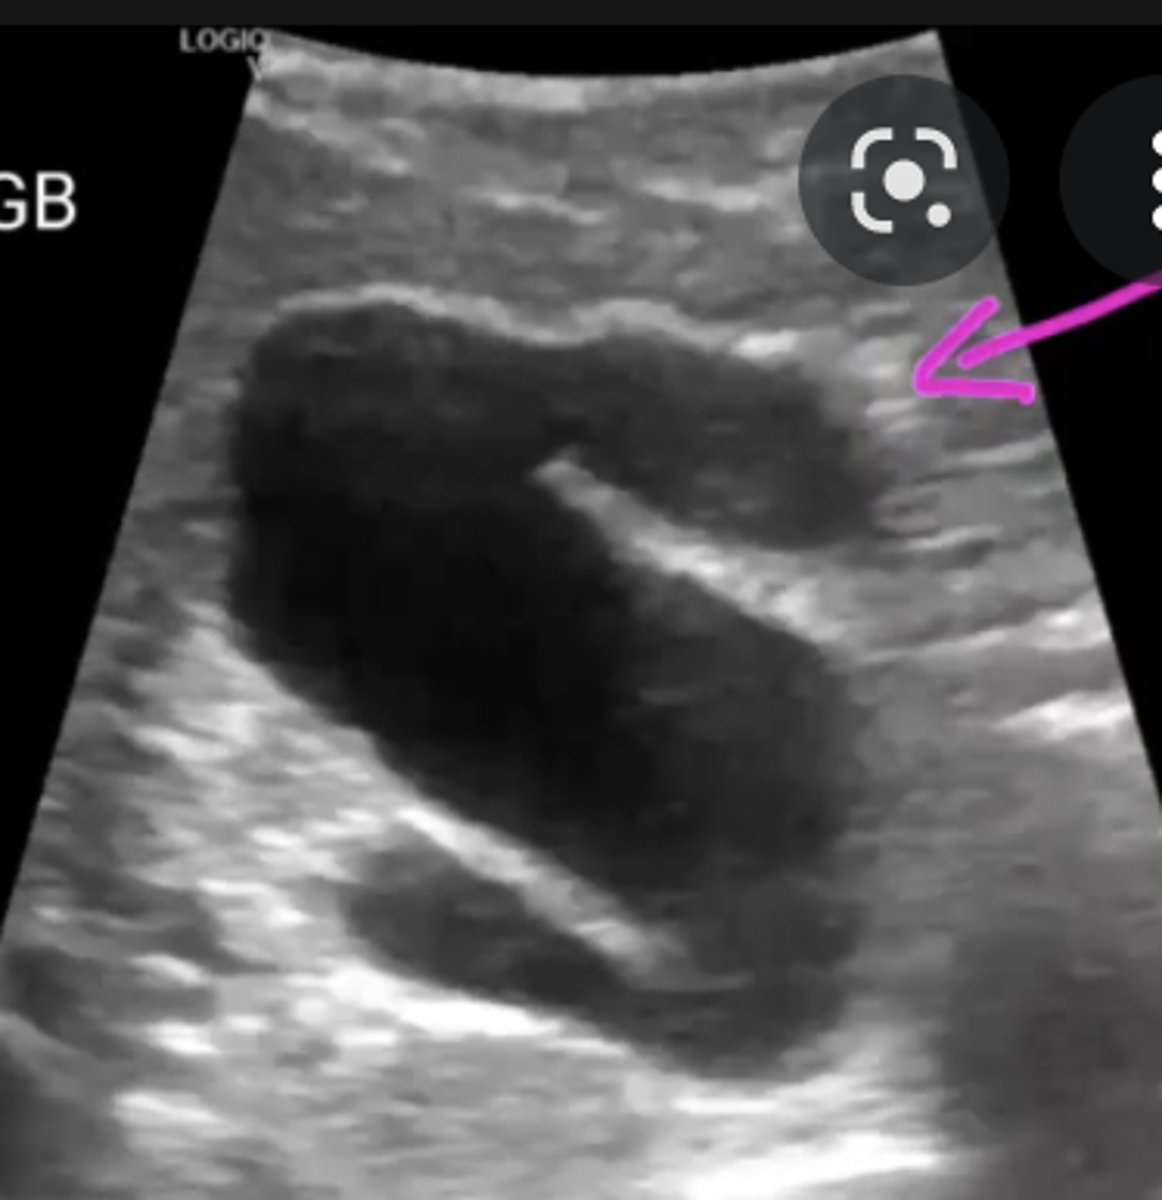

In the sagittal plane, the GB appears as an:

anechoic, pear-shaped structure located anterior to the right kidney and lateral to the head of the pancreas and duodenum

In the transverse plane, the GB appears as an:

anechoic and rounded

landmarks for identifying GB

Interlobar fissure/Main Lobar Fissure - appears as echogenic

linear structure connecting GB to MPV.